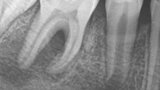

Fig. 2c: Conventional radiograph of an endodontically treated tooth #11 and cold-sensitive tooth #12 compared with CBCT imaging showing the presence of a large apical bone defect (taken at a two-day interval).

Fig. 3: Pre-op radiograph of tooth #46 showed a large area affected by periapical periodontitis going up into the furcation.